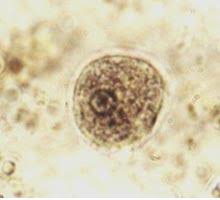

parásitos diversos como amibas, Trichomonas, Balantidum coli, Enterobius vermicularis, Ascaris lumbricoides etc.

Las causas de estas infecciones son muy variadas entre las que se incluyen el uso de ropa interior muy ajustada y de materiales sintéticos como lycra que favorecen el aumento de temperatura, hasta prácticas sexuales como el sexo orogenital, anal genital, promiscuidad sexual, o por simple continuidad del ano con la vagína, lo que facilitaría el paso de organismos del tracto digestivo a la zona vaginal, entre las infecciones de tipo viral que es posible detectar con la prueba de papanicolau estan el herpes y el VPH.